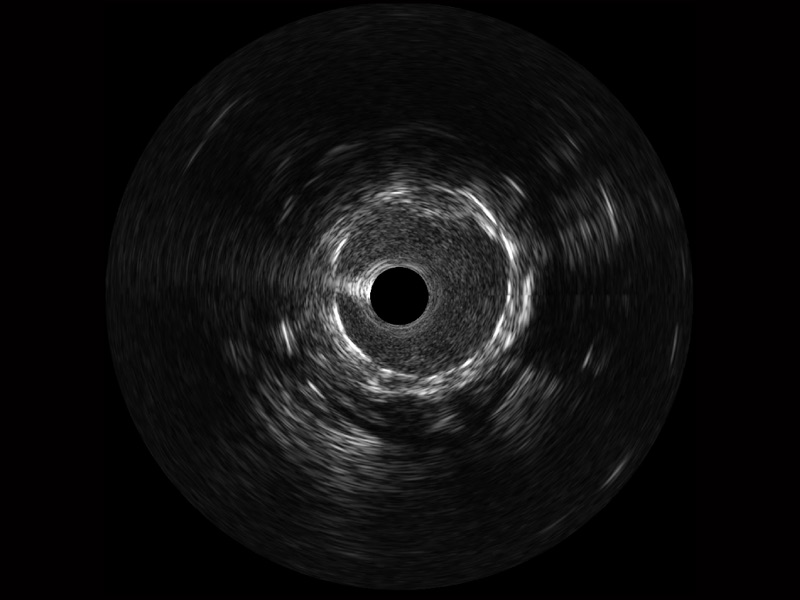

DB中国旗舰官方网站宽频IVUS图像

传统IVUS图像

对比传统IVUS导管成像,DB中国旗舰官方网站宽频IVUS图像的近场支架梁显影更细腻,远场中膜外血管仍清晰可辨,兼顾远中近,兼顾分辨力与穿透深度